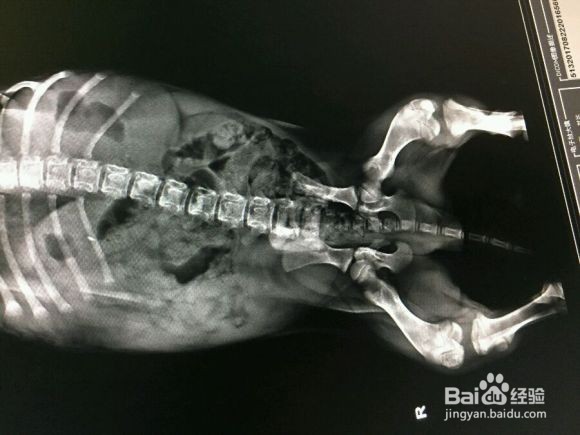

1、首先这种情况最好去医院,避免触碰伤口导致感染或进一步损伤。将狗狗带到安全、舒适的环境后,就需要及时检查伤势

2、如果伤势严重还需先用支架固定腿部,可以用支架或者坚硬物来固定下狗子的腿,可以去药房买个聚维酮碘给狗子伤口消毒然后包扎固定

3、严重的话狗子几乎无法自愈,后期饮食方面多注意,多补补钙,希望可以帮到你。